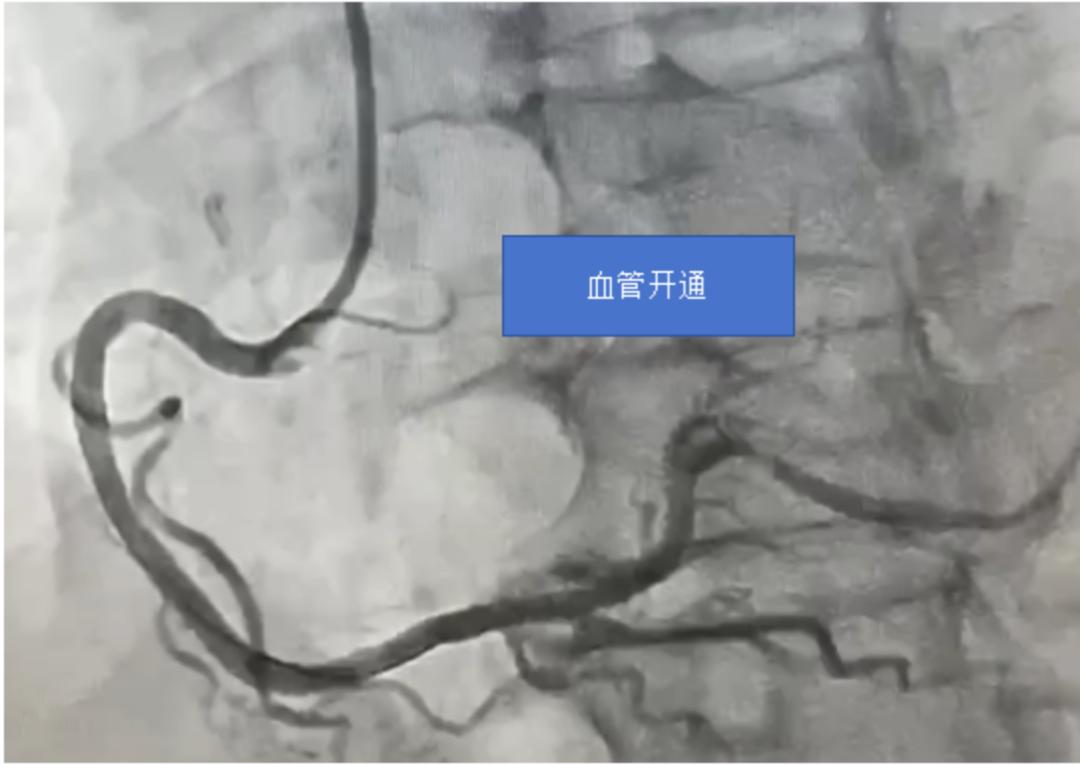

与此同时,急诊科主治医师张彬立刻赶往保石镇卫生院,无缝对接,将患者快速转送至我院。患者到达后,心血管内科介入团队迅速行动,与时间赛跑。他们争分夺秒,迎难而上,凭借精湛的医术与默契的配合, 从患者抵达医院门口到导引导丝通过闭塞血管(D - to - W 时间,国家胸痛中心要求 90 分钟以内),仅仅用了 23 分钟;球囊扩张时间(D - to - B 时间)也仅为 35 分钟。在各急救单位、部门的紧密协作下,患者的生命得以快速而有效地挽救。